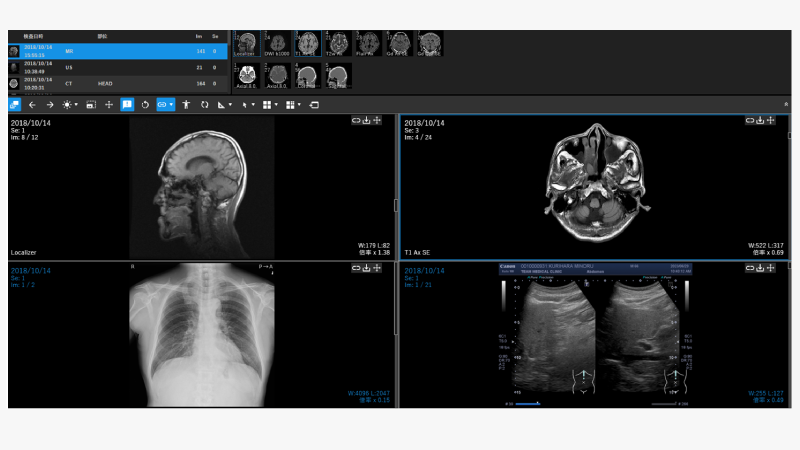

■DICOM画像表示Viewer M-Viewer

完全WEB DICOM対応で画像の高速表示を実現した高機能DICOM Viewerです。

OSを問わずブラウザのみで使用できるため、使用場所や端末を問いません。

また、直感的に使える操作により作業効率を向上します。